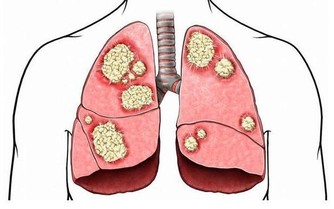

如果發現腹部也有青筋,並且有曲張的現象,就要提高警惕了,可能是出現了腹水,及時去醫院檢查。